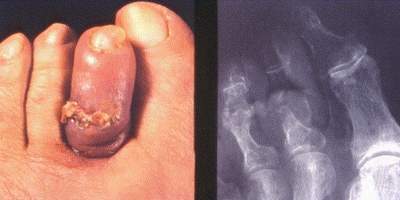

Qu’est ce que c’est?

Ostéite du 2e orteil. Fistule pathognomonique